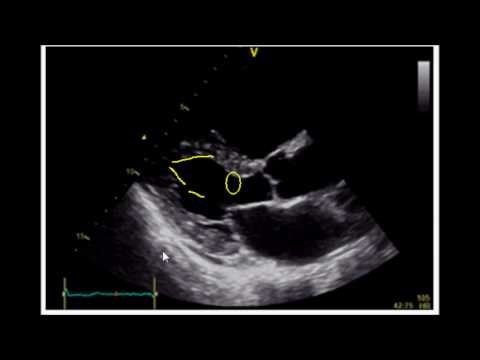

В этой лекции из нашего курса ультразвуковой диагностики доктор Мэтью Таббут, доктор медицинских наук, рассказывает о применении метода фракционного укорочения при ультразвуковом исследовании сердца у постели больного для оценки фракции выброса левого желудочка в отделении неотложной помощи. Узнайте, как проводить сканирование, интерпретировать результаты и распознавать распространённые ошибки, чтобы уверенно применять этот метод у пациентов с подозрением на сердечную недостаточность. --- Следите за нами в интернете и социальных сетях: ✅ Сайт: ✅ Twitter: / mh_emultrasound ✅ Instagram: / mh_emultrasound --- Это официальный аккаунт отделения ультразвуковой диагностики неотложной медицинской помощи Университета Кейс Вестерн Резерв и Медицинского центра MetroHealth. Видеоролики не являются медицинскими рекомендациями или взглядами/политикой этих учреждений.